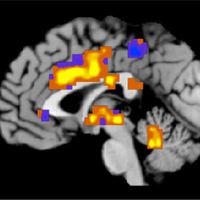

Fiziksel acının miktarı, ilk kez objektif olarak ölçüldü